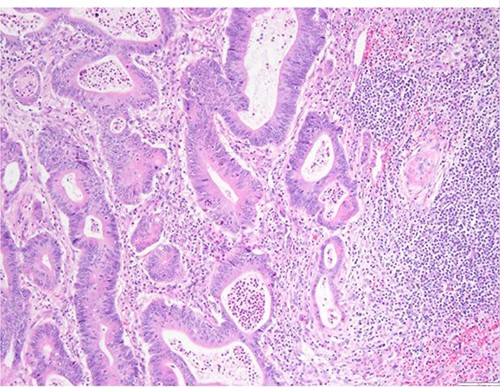

Surgical specimen: splenectomy; microscopy, HE; spleen parenchyma infiltrated by well-formed neoplastic glandular structures composed of cells with ‘pencillated’ and atypical nuclei, with nucleoli, apoptosis and mitotic figures, consistent with an intestinal origin (metastatic colorectal adenocarcinoma).

Surgical specimen: splenectomy; microscopy, HE; spleen parenchyma infiltrated by well-formed neoplastic glandular structures composed of cells with ‘pencillated’ and atypical nuclei, with nucleoli, apoptosis, and mitotic figures, consistent with an intestinal origin (metastatic colorectal adenocarcinoma).